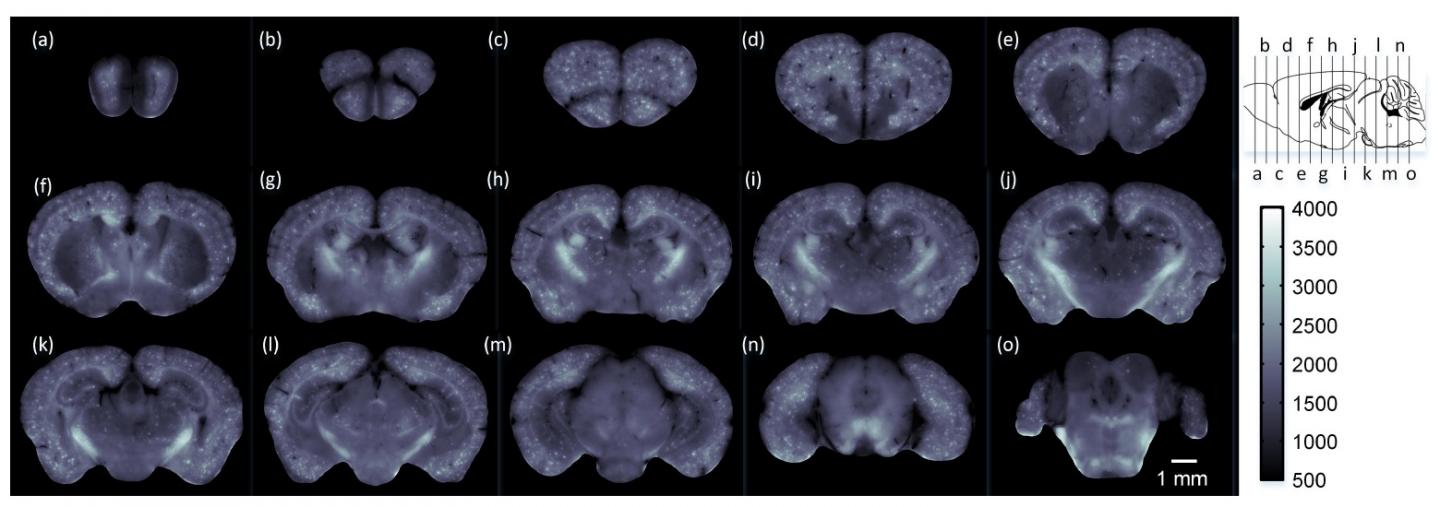

To demonstrate the ability of cryo-MOST to image the brain-wide distribution of senile plaques, the researchers used it to image a whole brain from a 17-month APP/PS1 mouse model of Alzheimer's disease.

"The images from an aged Alzheimer's disease mouse revealed that senile plaques have spread to the whole brain," said Yuan. "This indicates that the disease not only hurts memory and intelligence, but may also cause an overall deterioration of other brain functions."

The system used in the paper has a lateral resolution of 1.072 microns and an axial resolution of 17.152 microns when detecting fluorescence at a wavelength of 536 nm. The researchers say that these parameters could be further improved by using a better microscope.